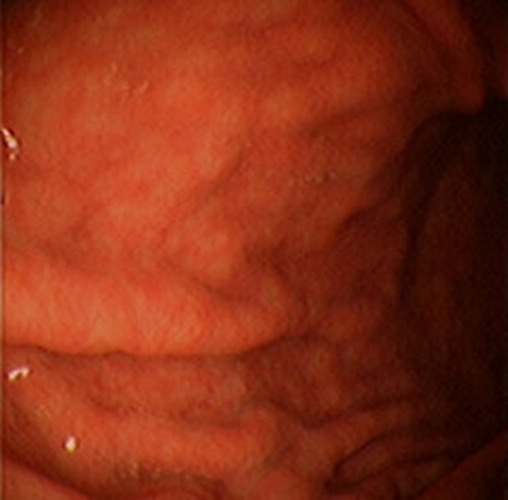

急性胃炎圖片

急性胃炎陽性表現

急性胃炎陽性的表現的

急性胃炎陽性的表現